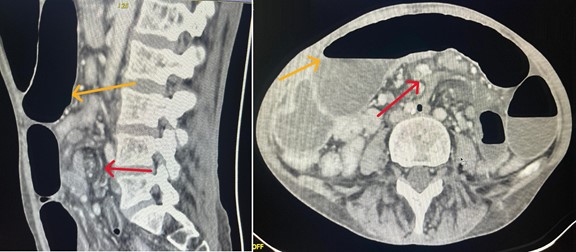

Abdominal Computed Tomography (CT) demonstrated small bowel distension with a characteristic mesenteric whirl sign, consistent with volvulus, associated with segmental bowel wall thickening without signs of intestinal ischemia (Figure 1).

Figure 1: CT scan showing the mesenteric whirl sign (red arrow) and small bowel distension with air–fluid levels (yellow arrow).

From a diagnostic standpoint, CT scan is the imaging modality of choice. The mesenteric whirl sign is considered pathognomonic, reflecting the twisting of bowel loops and mesenteric vessels around the vascular axis [7]. CT also al lows assessment of bowel viability by identifying signs of ischemia or impending necrosis.